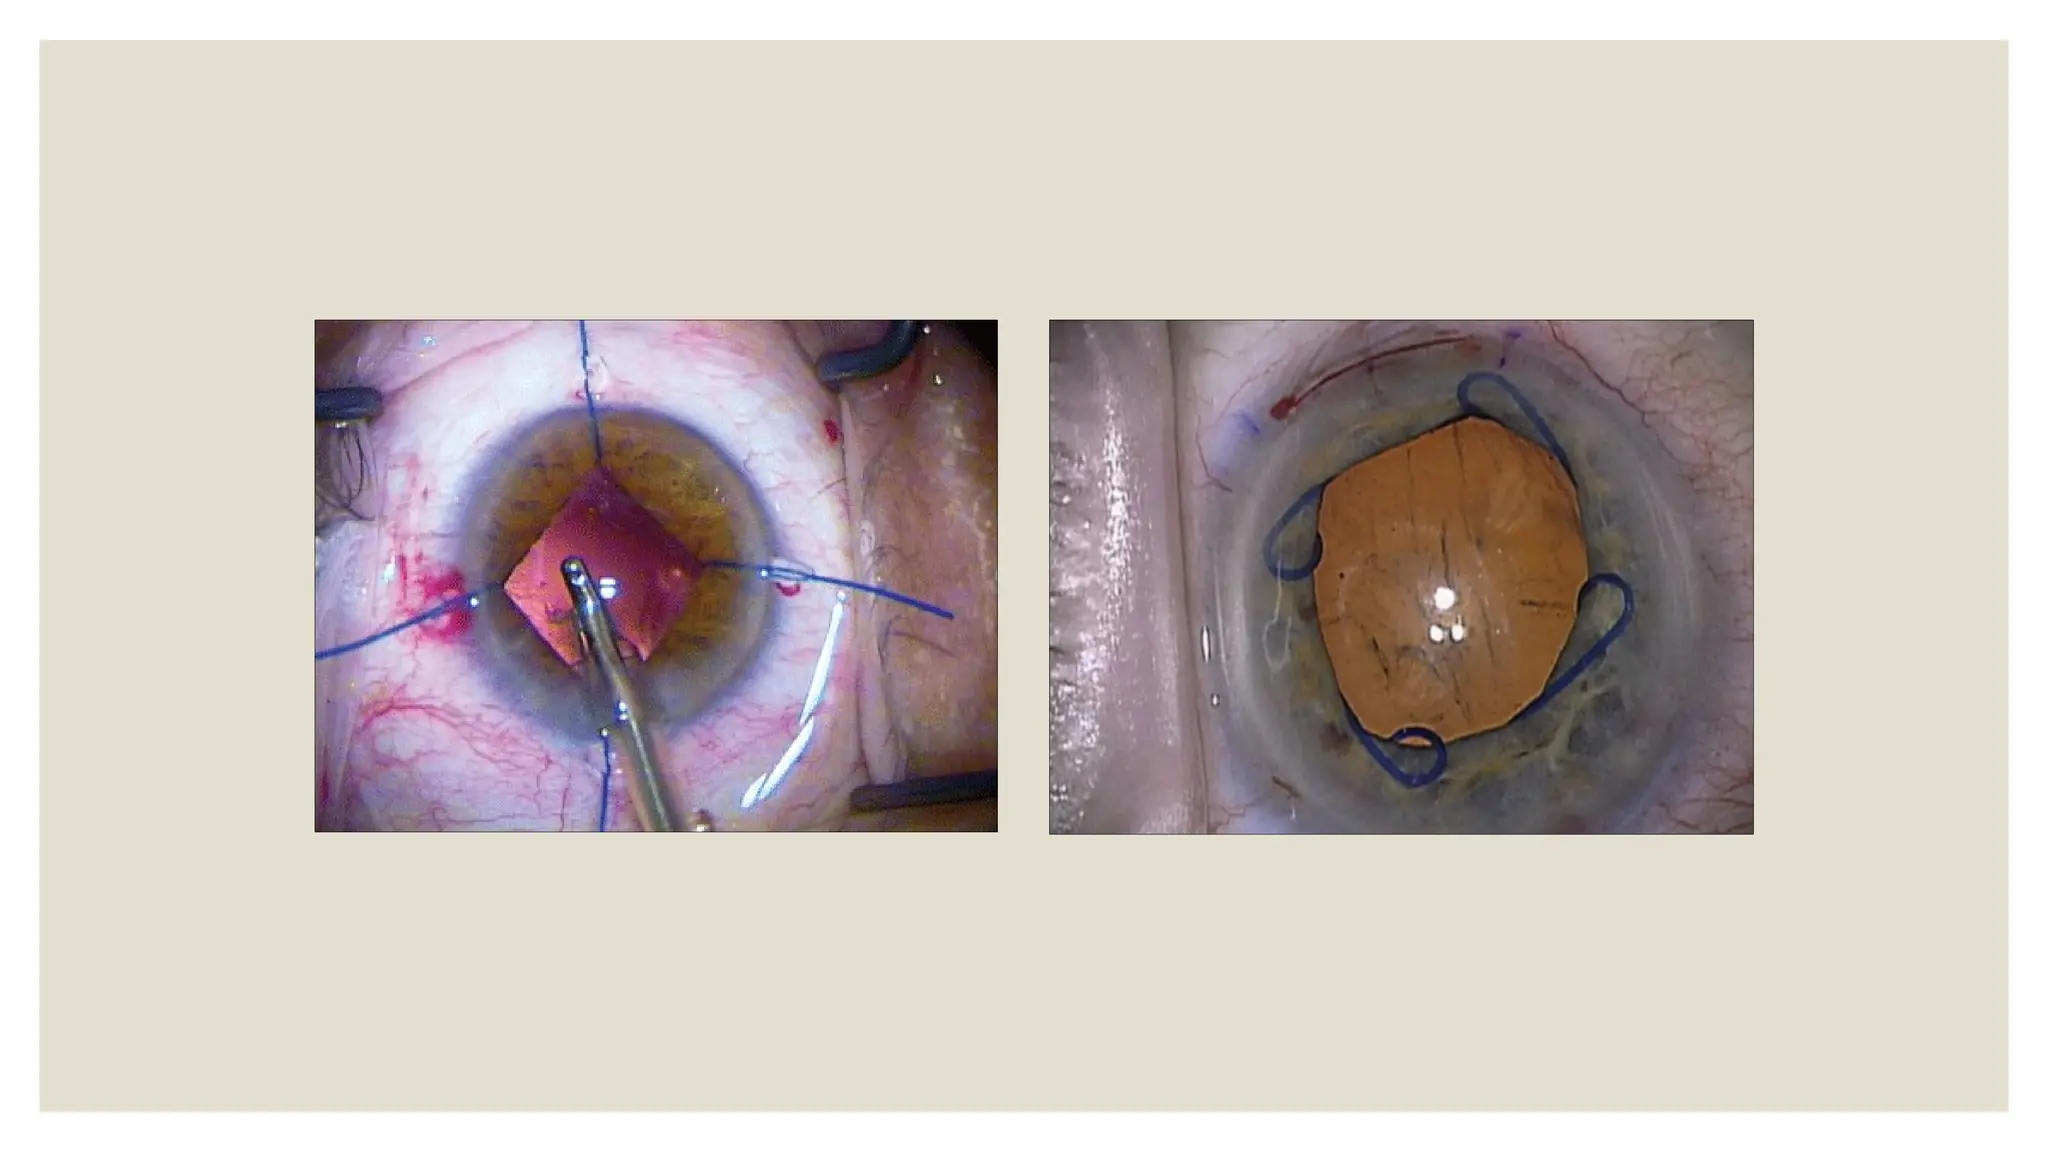

◦ Ghost cells : Tan and khaki-colored, less pliable, spherical freely

TT:

Ineffective to standard medication

Persistent IOP rise- AC wash

Ghost Cell Glaucoma ◦Vitreous hemorrhage after 1-3 weeks ◦ Ghost cells : Tan and khaki-colored, less pliable, spherical freely mobile TT: Ineffective to standard medication Persistent IOP rise- AC wash Recurrent IOP rise- Vitrectomy